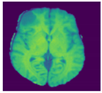

A brain tumor can be defined as a cancerous or noncancerous mass or development of abnormal cells in the brain. Gliomas can be categorized into High-Grade Glioma (HGG) and Low-Grade Glioma (LGG), based on the pathological assessment of the tumor. Brain tumor segmentation seeks to separate healthy tissue from tumorous regions. This is a crucial step in analysis and treatment planning to improve the possibility of effective treatment. Nowadays, biological science has emerged with several extended research problems under the category of Digital Image Processing (DIP). The detection of the tumor and its classification, detection of the cancerous region and its classification, testing, and inspecting crucial parts of the human body are some applications that fall under this category. Out of various medical science problems, automatic brain tumor segmentation and detection is of utmost importance, and efforts are being made in order to effectively handle this problem. A January 2020 Cancer.net editorial approved a report that estimated that this year, 23,890 adults, i.e., 13,590 males and 10,300 females, will be identified with cancerous tumors of the brain and spinal cord in the USA. In general, brain tumor diagnosis usually starts with Magnetic Resonance Imaging (MRI). The suspicious regions are separated using magnetic resonance segmentation using a complicated clinical imaging process. MRI is the most commonly used process that highlights the tumorous region in the brain, although brain tumor detection is still a manual process, examined and validated by experts. Thus, we require a compelling process to identify brain tumors in the early stage to save patients with high accuracy. There are some issues in the manual process, due to which the automatic detection of brain tumors becomes pivotal. Computer-aided detection of abnormal growth of tissue is primarily motivated by the necessity of reducing human error and thus achieving maximum possible accuracy. Using automated algorithms for the accurate and robust predictions of overall survival for patients diagnosed with gliomas can provide valuable guidance for diagnosis and necessary treatment. Furthermore, there is a lack of skilled Oncologists and Neurologists, especially in developing countries. According to a report in 2018, the country is facing a severe shortage of caregivers, with merely 2000 oncologists looking after around 10 million patients (https://timesofindia.indiatimes.com/india/India-has-just-2000-oncologists-for-10-million-patients/articleshow/50842842.cms). Owing to the presence of abnormalities, no conventional technique can be developed for the segmentation of brain tumors in the medical field. Generally, magnetic resonance image (MRI) scans are utilized for the proper examination and diagnosis of brain tumors. This study systematically works on the detection of brain tumors using MRI images []. Owing to the profound significance of machine learning and deep learning, a vast number of methods have been developed, mostly using a specific technique, i.e., machine learning or deep learning []. Despite initiating a breakthrough in handling tumor detection tasks, existing applied deep learning models have some drawbacks. CNN-based deep learning techniques require high volume data, which makes it a complex and expensive task. Massive features are necessary to train tumor detection and segmentation accurately. However, the U-net model of CNN has shown great help in prognosticating in medical image segmentation. In recent literature, numerous works are done either using variation in U-Net architecture or with some pre/post-filtering for outcome improvisation. A Multi-Inception-UNet architecture is proposed to improve scalability and is applied to BraTs 2015, 2017, and 2019 datasets []. This is considered the latest work done in this same direction with the help of this same U-Net Model. MRI Brain Tumor segmentation is validated using 3D-UNet on the BraTs’20 dataset, where the author achieved an accuracy of 0.83 on the training set and 0.82 on the validation set []. The proposed work is somewhat motivated by the work done by Jurdi et al. in June 2020; in their work, U-Net with Bounding Box Prior is applied to two public datasets—SegTHOR is Computed Tomography (CT) images and another Cardiac dataset is a mono-modal MRI dataset. A bounding box (BB) filter is inserted at the BBConV Layer, by which researchers can achieve approximately 98.32% average dice coefficient []. Henceforth, in this study, a systematic process is performed for the detection of brain tumors using MRI images. The experimentation uses U-Net to exhibit the knowledge of deep learning models for tumor image segmentation. The deep learning model is applied for MRI segmentation on the BraTS 2018 dataset (https://www.med.upenn.edu/sbia/brats2018/data.html), which contains four different MRI modalities—T1, T2, T1Gd, and FLAIR of each patient (see Figure 1).

Figure 1.

A sample set of T1, T1-GD, T2, and T2 Flair images (Source: BraTS 2018 Dataset).

Corresponding to each patient, the segmented tumor region and OT (ground truth of tumor segmentation) are stated. Although experiments are primarily carried out on the BraTS dataset, a list of datasets used to perform brain tumor detection tasks is also tabulated in Table 1 for the readers’ point of view.